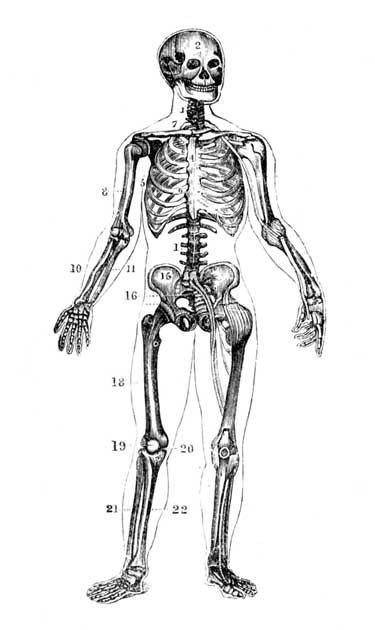

1. Vertebral Column; 2. Skull; 4. Sternum; 7. Collar Bone; 15. Hip Bone; 16. Sacrum; 18. Femur; 19. Knee Pan; 21. Fibula; 22. Tibia; 8. Humerus; 10. Radius; 11. Ulna.

Fig. 1.—A bit of the inner coat of the small intestine.

Fine threads of blood vessels (capillaries) take it up from the stomach and intestines. Also along the intestines there are little projections (villi), through which the food passes into a blood stream leading to the liver, where the blood is then purified. These projections also contain lacteals or little vessels containing blood without its red corpuscles. A duct carries this colourless blood mixed with absorbed food to the left side of the neck, where it empties into the blood stream. These lacteals have a special affinity for the fat of the food. Most of the rest of the food, including the proteid and the carbohydrate or starchy portion now in the form of sugar, passes into the capillaries, and then is led to the liver.

The liver will not let through more sugar than is required, storing it up for future use. It also acts as a careful guardian, by arresting many poisons which would otherwise pass into the general circulation. The liver requires for the proper performance of its functions plenty of pure blood, hence the necessity for fresh air and exercise, that the lungs may work well. The liver is easily influenced by alcoholic beverages, and by getting too hard work to do through eating rich foods. A consideration of this delicate and intricate process, whereby the digested food is absorbed, will show that badly-digested food can not hope to be well assimilated, consequently attention should be paid to the quantity and quality of the food we eat (see Digestion; Diet).

Fig. 2.—Two villi containing lacteals. The white canals are lacteals, the darker lines indicate blood vessels (capillaries). Magnified 100 diameters.

(From "Quain's Anatomy.")

Whatever thus makes living substance is nourishment; whatever fails to do so is not. If food be taken, and even digested, without being thus assimilated, it becomes an injury to a patient instead of a help. In cases of fever, inflammatory disease, or wasting sores, much rich food feeds the fire. It is like laying rafters on the roof of a burning house for purposes of repair. In such a case small quantities of milk, or milk and hot water (see Digestion), represent the total food which can be effectively used in the body. We write on this subject that in treatment our friends may watch not to injure by making the blood too rich in elements which the system cannot usefully assimilate. Such foods as oatmeal jelly and wheaten porridge will often furnish more real nourishment than pounds of bread, beef, and potatoes. A little careful thought will guide to correct treatment in this matter. An easily assimilated diet is found in Saltcoats biscuits and hot water; many inveterate stomach troubles have yielded to this, when taken as sole diet for some weeks (see Biscuits and Water).

Treatment may also be given for lack of assimilative power. The back, especially on either side of the spine, is rubbed with gentle pressure and hot olive oil. This pressure is so applied that a genial heat arises along the whole spinal column. This done twice a day, for half-an-hour at a time, and continued for several weeks, will markedly restore assimilative power. Cases which have been perfectly helpless for eight and even ten years are cured by this simple method, sufficiently and carefully followed.

We had a patient who was stout, but weak and weary, with the muscles slack and showing loss of power. The effect of back-rubbing, accompanied by easily assimilated food in small quantities and often, was to lessen his weight by a considerable amount. But the muscular power at once began to increase, and the man was soon like one made anew. Digestion had not been impaired in this case, but the blood formed by it was not converted into good living substance. Sight and hearing have even been restored by these means when the failure in eye or ear has been due to waste material accumulating, as frequently is the case.

In connection with many troubles, what may be called local assimilation has to be considered. A foot, say, with a bad abscess or diseased bone (see Pain, Severe) is cured by hot bathing and pressure. From a shrunken and feeble limb, the leg grows to a healthy and strong one. This occurs because the heat and pressure have so stimulated its vitality that the material supplied by the blood can be utilised in the leg for purposes of healthy growth. So with any other part of the body. Such diet as we have indicated supplies easily assimilated substance. The local heating, pressure, and bathing enable this substance to be utilised where it is needed. A little careful thought on this line will guide to proper treatment of almost any case where assimilation has failed, either locally or generally, and will lead the way to a method of cure.